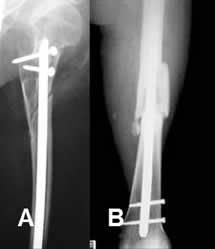

Fig 92. Clavo de Enders.

A: Rx AP. Fractura espiroidea y con angulación en valgo, de la diáfisis humeral.

B: Rx AP. Reducción abierta y fijación intramedular, con clavo de enders.